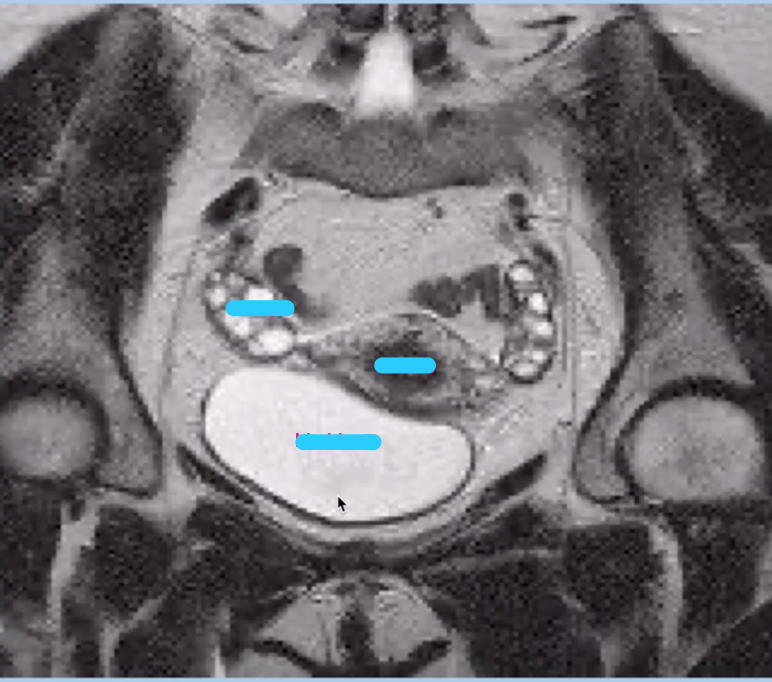

What type of imaging modality is this & fill in the blanks

MRI prostate, axial

Q

Coronal MRI